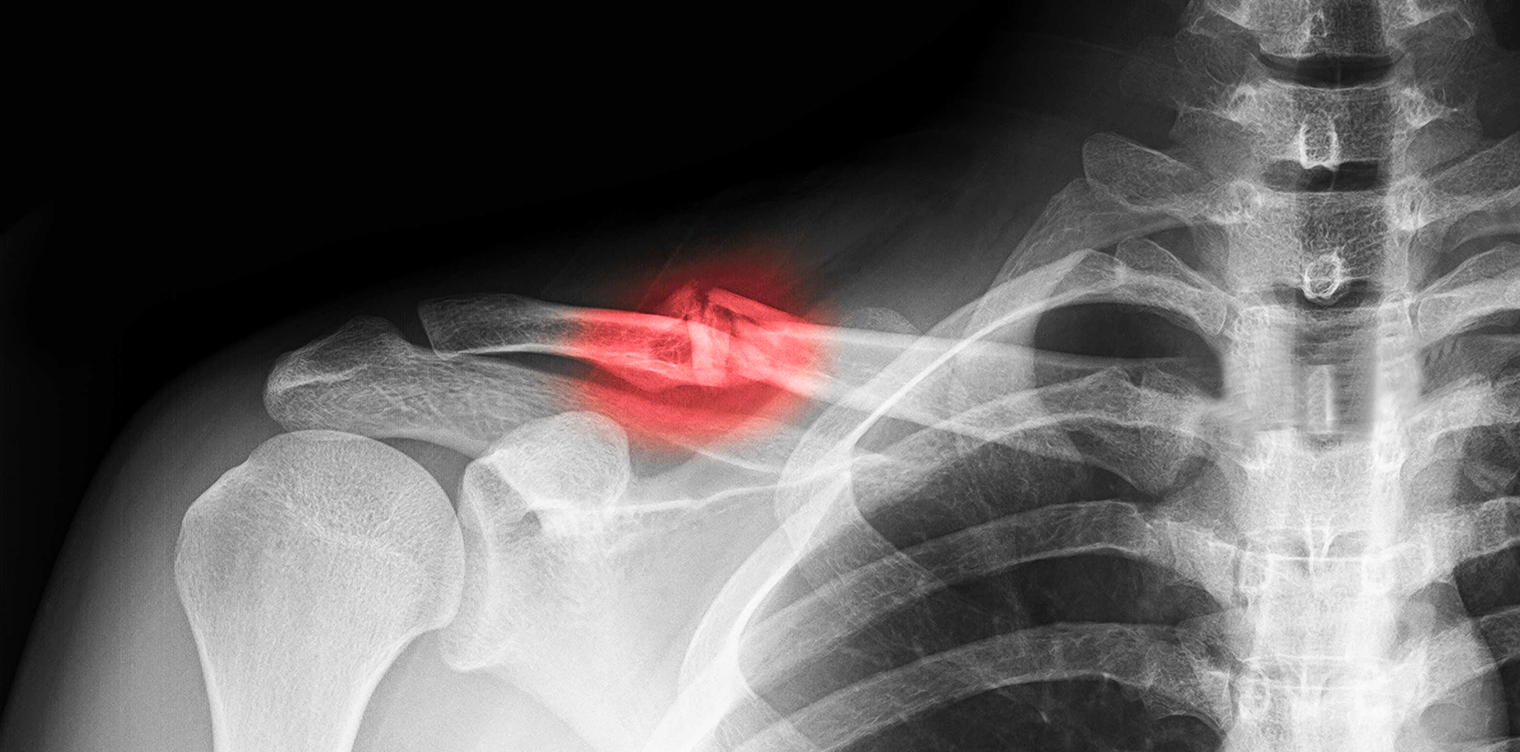

Image raon x montrant une fracture claviculaiure - fracture clavicule reeducation | IK Paris

Les fractures de la clavicule consistent en des lésions induites dans la plupart des cas par un traumatisme indirect, tel qu’une chute sur la main ou l’épaule qui survient souvent dans un contexte d’accident sportif. Fréquentes, notamment chez les enfants, elles nécessitent généralement une immobilisation de la clavicule pendant plusieurs semaines. Comment traiter et soigner une fracture de la clavicule ? On fait le point.

Fracture de la clavicule : généralités

La fracture de la clavicule est une pathologie assez fréquente, à la prise en charge assez simple dans l’ensemble. La douleur et l’impossibilité de bouger l’épaule sont les principaux symptômes. Une ecchymose et un œdème peuvent également être présents.

On rencontre plusieurs types de fractures de la clavicule, la plus commune étant la fracture du tiers moyen. Le traitement est dans la majorité des cas conservateur, avec une contention externe, autorisant une guérison sans séquelle. Toutefois, certaines fractures nécessitent un traitement chirurgical, avec réduction ouverte et ostéosynthèse.